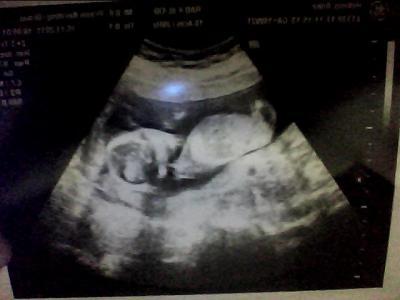

Hallo Es ist alles bestens, dem Krümel geht es gut und das Herzchen hat geschlagen. Ich war richtig erleichtert, jetzt mache ich mir keine Gedanken mehr ob noch was passieren kann und kann mich voll und ganz auf die SS kkonzentrieren. Ein Outing gab es leider nichr, da entweder ein Bein oder die Nabelschnur im Weg waren. Jetzt hoffe ich am 13.12. ein Outing zubekommen, will doch wissen was es wird. Dann bin ich in der 20. SSW und da muß man doch was sehen, wenn Krümel es zulässt. Hier noch ein Bildchen vom Krümel. LG Anke

Schönes Bild und klasse das alles gut ist.